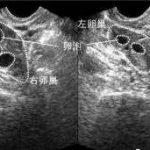

大家都知道,卵子和精子的结合才是生命的开始,所以卵子的质量和数量对泰国试管婴儿成功率还是有影响的。很多患者在做检查时发现基础卵泡少,此时患者朋友就比较担心,这样会影响泰国试管婴儿的成功率吗?